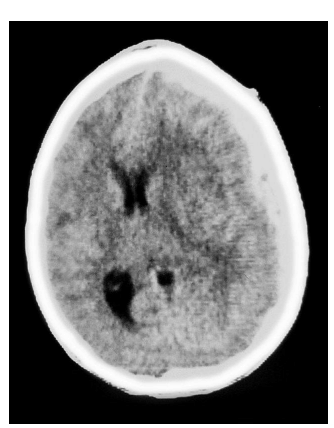

A tomografia evidenciou Hematoma Subdural Agudo, com efeito de massa, compressão ventricular e desvio de linha média.